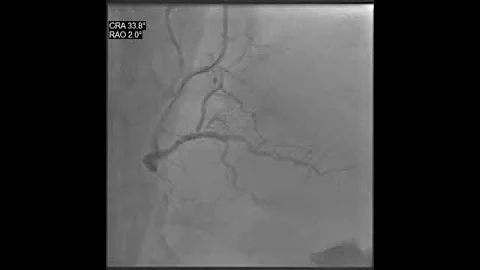

Primary PCI to LAD Patient presented with Acute Anterior Wall MI #Cardiology #MedEd #Foamed #USMLE #ACC #AHA ...